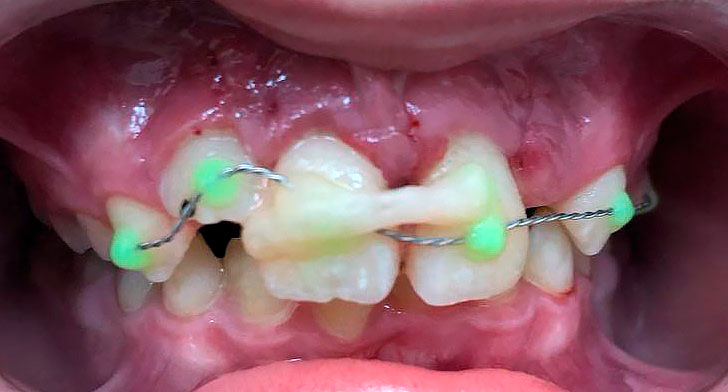

Осмотр полости рта: зубы 5.3, 6.3 прорезаны полностью, коронка интактная, подвижность отсутствует, зуб 1.2 в стадии прорезывания, имеет вестибулоположение, коронка интактная, подвижность отсутствует, зуб 2.2 в полости рта не прорезался. Зуб 6.4 в полости рта отсутствует, зуб 6.5 коронка интактная, подвижность отсутствует. Зубы 1.1, 2.1: визуализируется диастема, коронки зубов интактные, в цвете не изменены, патологическая подвижность 2 степени, перкуссия болезненная. Холодовая проба: положительная кратковременная реакция. При зондировании пародонтологическим зондом (вестибулярно и нёбно в трех точках) определяются патологические зубодесневые карманы глубиной до 13 мм. Гнойное отделяемое отсутствует. Краевая слизистая в области зубов 1.1, 2.1 гиперемирована. Фенотип десны во фронтальном отделе верхней челюсти толстый (Рисунки 1-3)

Рисунок 1. Клиническая картина в полости рта, после проведения местной анестезии.

Визуализированы и удалены 2 эластических кольца из области апикальной трети зубов 1.1, 2.1 путем захвата кольца иглодержателем и рассечения ножницами, антисептическая обработка 0.05% раствором Хлоргексидина. Гнойного отделяемого не обнаружено, открытый кюретаж не проводился (Рисунки 11, 12).

Рисунок 11. Визуализированы и удалены два эластических кольца из апикальной трети пародонта зубов 1.1, 2.1.

Рисунок 12. Эластические кольца, удаленные из пародонта зубов 1.1, 2.1